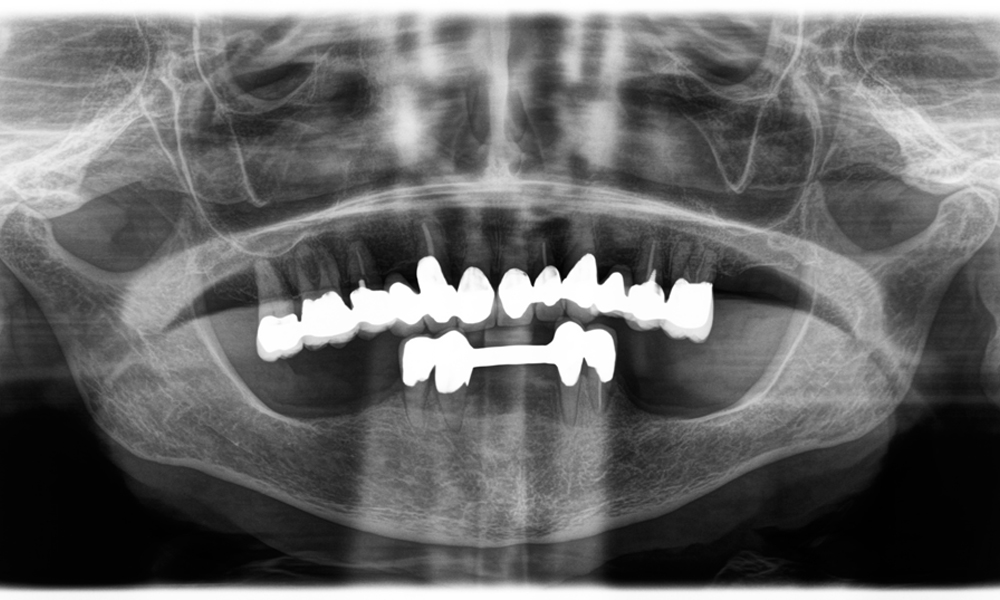

Un deuxième cas illustrant les capacités cliniques du Power Edition concernait le remplacement d'une couronne en zircone endommagée chez une patiente de 63 ans. La patiente présentait une facette ébréchée sur sa couronne en zircone vieille de 20 ans sur la dent 6. Malgré l'emplacement postérieur, la patiente trouvait le défaut gênant et demandait une nouvelle restauration.

Le Power Edition a permis un sectionnement précis, grâce à un couple accru et un refroidissement amélioré qui ont contribué à l'ablation contrôlée de la couronne sans perte importante de matière. Le système de serrage et le couple amélioré se sont avérés essentiels dans ce processus.

Une radiographie montrant des dents et une couronne en zircone, sur fond noir.

Figure 2 : Remplacement d'une couronne en zircone endommagée : retrait précis et renouvellement d'une couronne en zircone endommagée sur la dent 6 avec une perte de matière minimale.